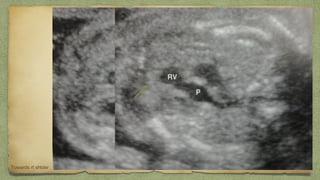

๏ฑ 2 ventricles/ walls of equal size

๏ฑ 2 atria / walls of equal size

๏ฑ Foramen ovale moving in left atrium

๏ฑ Pulmonary veins entering left atrium

๏ฑ Motion of mitral valves (left side) regular

๏ฑ Motion of tricuspid valves (right side) regular

๏ฑ Continuity of interventri septum